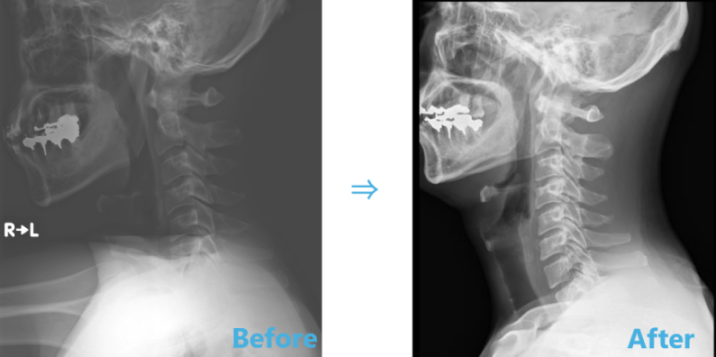

上の写真は実際の当院の患者さまのレントゲンです。

当初の画像と比べると(写真左)、ストレートネックが随分改善されていました(写真右)。

もちろん、お体の症状や姿勢も改善されておられます。

定期的に通院されて、1年半以上たっております。